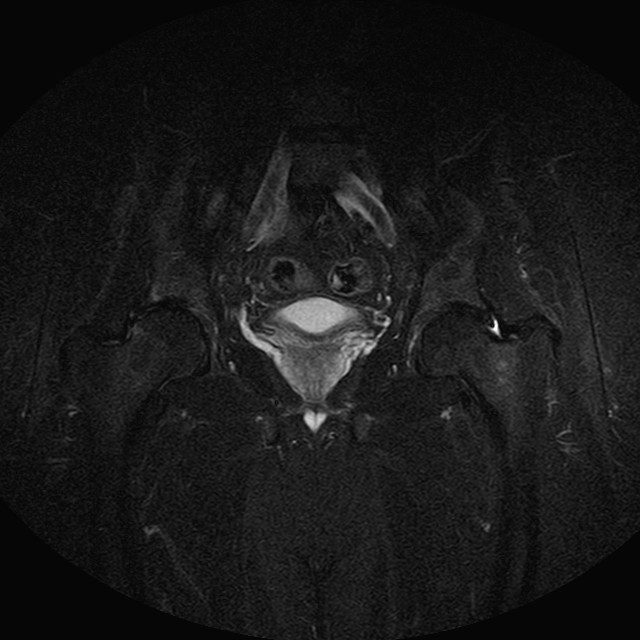

Esami: RMN BACINO

eSTIR

Evidenti e simmetriche alterazioni osteofitosiche in regione coxo femorale con riduzione delle rime articolari. Degenerazione completa del cercine glenoideo. Non attuali segni di versamento articolare. Non segni di edema osseo che escludono attuale algodistrofia od osteonecrosi. Lieve e simmetrica riduzione del trofismo della muscolatura glutea.